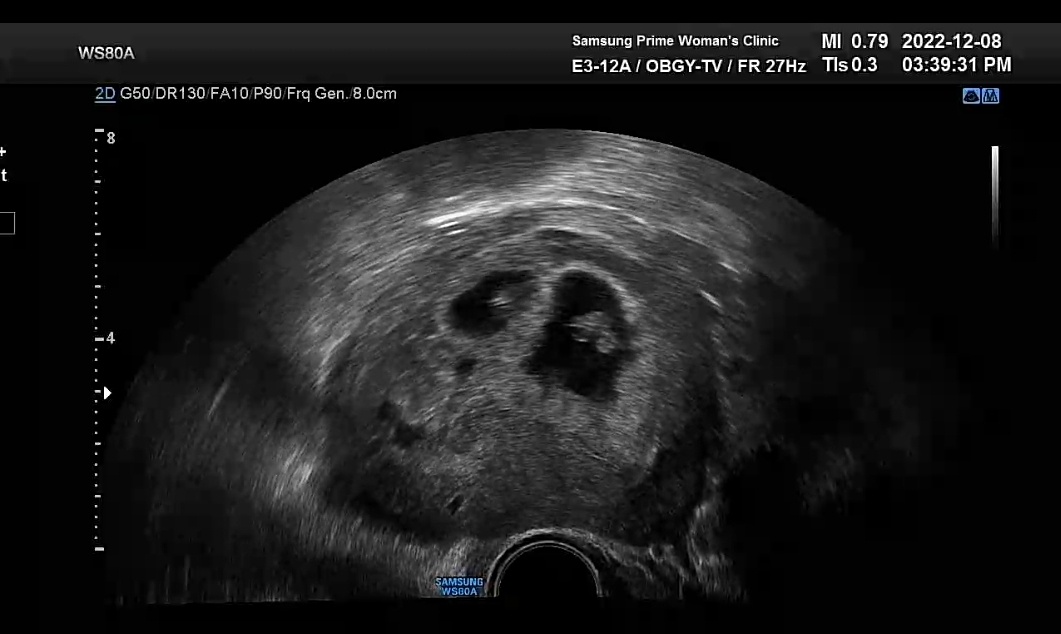

임신 초기에는 이런저런 변수들이 많다고 하여 안정기라는 12주에 접어들 때까지 최대한 조심하며 지내고 있는중인데 어느덧 7주가 되었다.

그러다 임신 7주차에 아기 심장소리를 병원에서 듣고 오니 이제서야 드디어 실감이 나기 시작했다.

초음파 보니 아직은 아주 작은 우리 아가들의 심장이 콩닥콩닥 열심히 뛰는 모습이 보였다.

작은 우리 아가들 열심히 잘 자라주고 있구나 하는 생각에 우리 아가들이 기특하기까지 했다.